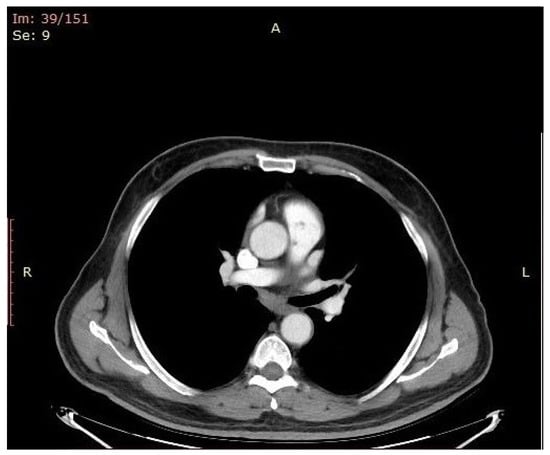

2. The Case